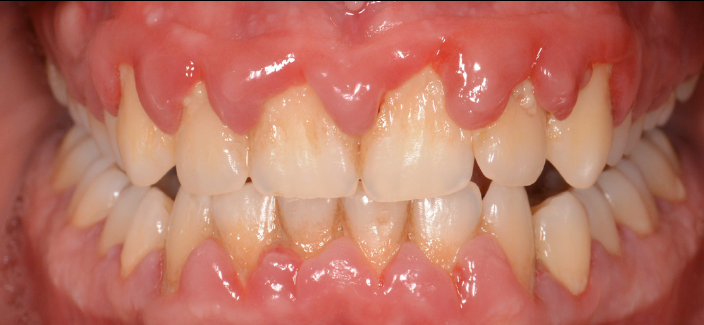

Cel mai vulnerabil punct al parodonțiului este șanțul gingival, ce se află la baza dintelui, între acesta și marginea gingivală liberă. Placa bacteriană și tartrul neîndepărtate corect printr-o igienă riguroasă se acumulează la acest nivel și reprezintă cauza declanșatoare a unei inflamații parodontale. Trebuie de asemenea înțeles de ce placa bacteriană are un efect distructiv asupra țesuturilor dentare: o parte din bacteriile prezente în cavitatea orală ce au ca principal suport nutritiv resturile alimentare îndepărtate prin periaj secretă o serie de toxine ce atacă suportul biologic al gazdei. (Fig. 5.1.1 și 5.1.2)

În cazul apariției oricărui tip de sângerare gingivală, pacientul este sfătuit să se adre- seze medicului parodontolog. Gingivita, fiind prima etapă inflamatorie din parcursul bolii parodontale, este complet reversibilă, atât timp cât este identificată precoce. (Fig. 5.1.3, 5.1.4)